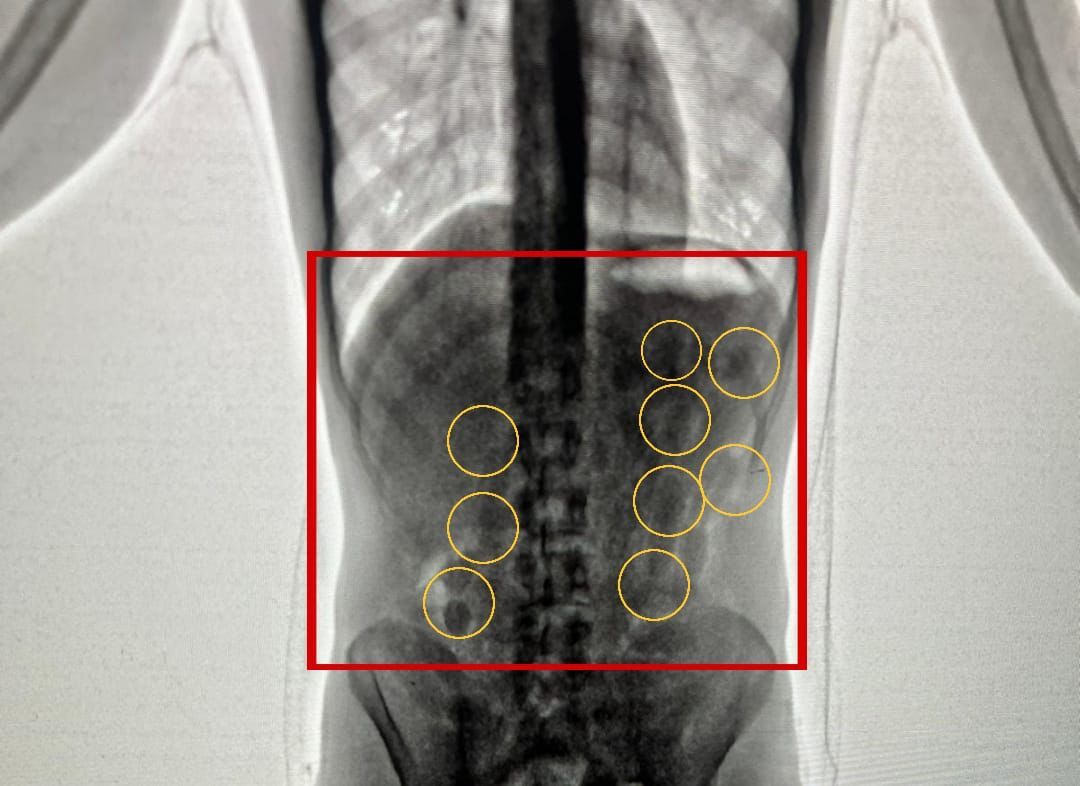

بين الناطق الاعلامي باسم مديرية الأمن العام أن كوادر إدارة مكافحة المخدرات أحبطت في مطار الملكة علياء الدولي محاولة تهريب 2 كغم من مادة الكوكايين المخدرة داخل أحشاء شخصين من جنسية أجنبية.

وبعد تفتيشهما والكشف عليهما بواسطة الاجهزة اللازمة اكتُشف وجود كميات من المواد المخدرة داخل أحشائهما ، وجرى إخراج هذه المواد بالطرق الطبية، وقُدرت ب 2 كغم من مادة الكوكايين المخدرة .